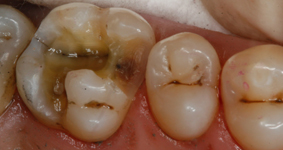

Система состоит из светового зонда и очков с фильтрами, которые можно надевать на обычные рецептурные очки. С помощью зонда Facelight вы просто освещаете полость – практически так же, как при использовании лампы для полимеризации. Метаболический процесс, происходящий в бактериях, оставляет порфирины как продукт метаболизма. Они создают четко различимую красную флюоресценцию в ультрафиолетовом свете. Здоровое зубное вещество можно отличить по характерной для него зеленой флюоресценции. Стоматолог видит и может четко выделять области, инфицированные кариесом, которые затем можно селективно удалять в процессе удаления кариеса.

Наш опыт применения Facelight показал, что с его помощью можно увидеть больше, чем со световым зондом Proface, в основном, при глубоком кариесе. Для классических зондов тонкие линии или пятна создают проблемы, их нельзя обнаружить и диагностировать.

Всего осмотру подверглись 14 пациентов с 67 полостями. После начального обследования с классическим зондом казалось, что все 67 полостей не содержат кариеса, но зонд Facelight показал, что 14 из этих 67 полостей не были полностью свободными от кариеса. Из этих 14 случаев, в которых наблюдался кариес, несмотря на положительный тест зондом, 11 были отнесены к глубокому кариесу. Этот предварительный результат наводит нас на размышления, поэтому мы продолжим собирать данные с помощью второго устройства Facelight. Благодаря этому намного повысится вероятность, что все пациенты в нашей практике пройдут обследование с использованием Facelight.